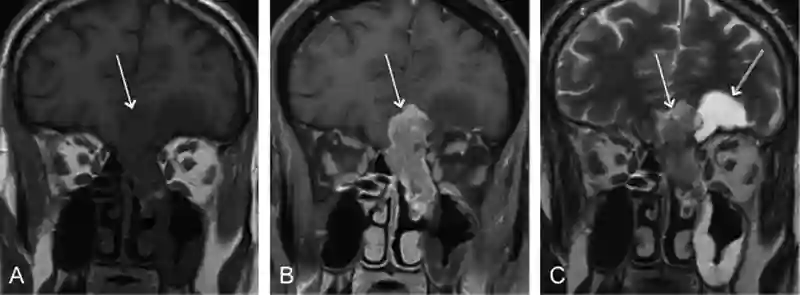

Im MRI zeigen sich Ästhesioneuroblastome in einer T1 gewichteten Sequenz mit einer mittleren bis hochen Signalintensität und es kommt zu einer heterogenen Anreicherung von Kontrastmittel2. Die Signalcharakteristik im MRI kann einem Meningeom ähnlich sein3.